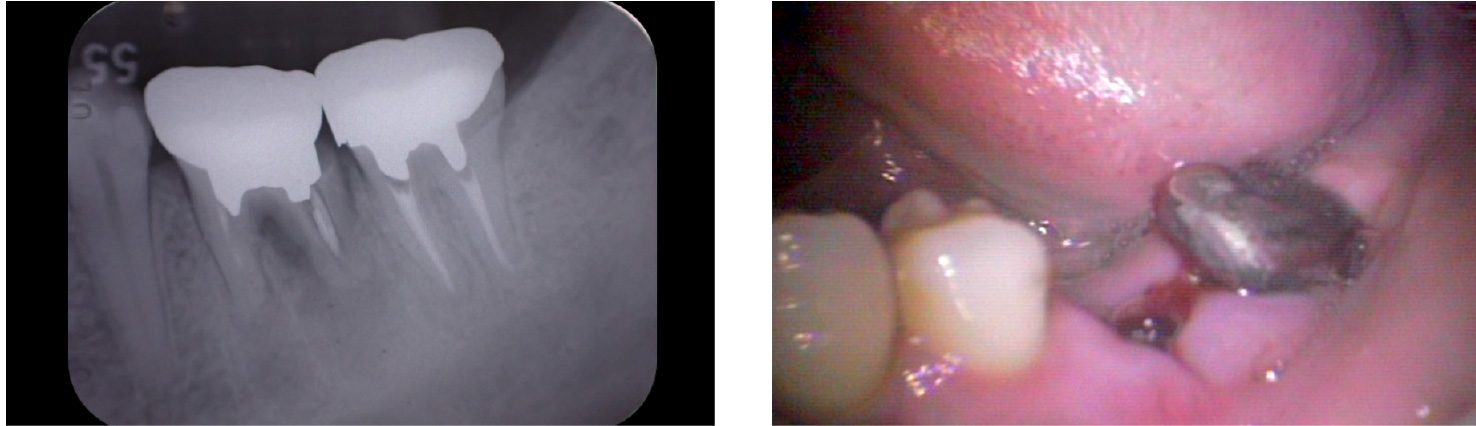

【インプラント埋入直後】

2009年10月40歳

【16年後】

2025年3月56歳

患者様の概要

- 治療当時

- 40歳

- 現在

- 56歳(術後16年経過)

- お悩み

-

「左下の奥歯で噛むと痛みがある」とご来院されました。

診査の結果、歯の根が割れてしまっていること(歯根破折)が痛みの原因と判明しました。 - 治療のポイント

- 割れてしまった歯の代わりにインプラントを1本埋入し、しっかりと噛める状態を取り戻しました。

治療から16年が経過しましたが、インプラントは非常に良い状態で安定しており、噛み合わせも問題ありません。

特筆すべきは、「インプラントがしっかりと噛む力を引き受けてくれたおかげで、 他のご自身の歯への負担が減り、この16年間でさらに歯を失うことがなかった」という点

現在も3~4ヶ月ごとに定期メンテナンス(パウダーによるクリーニング)に通って